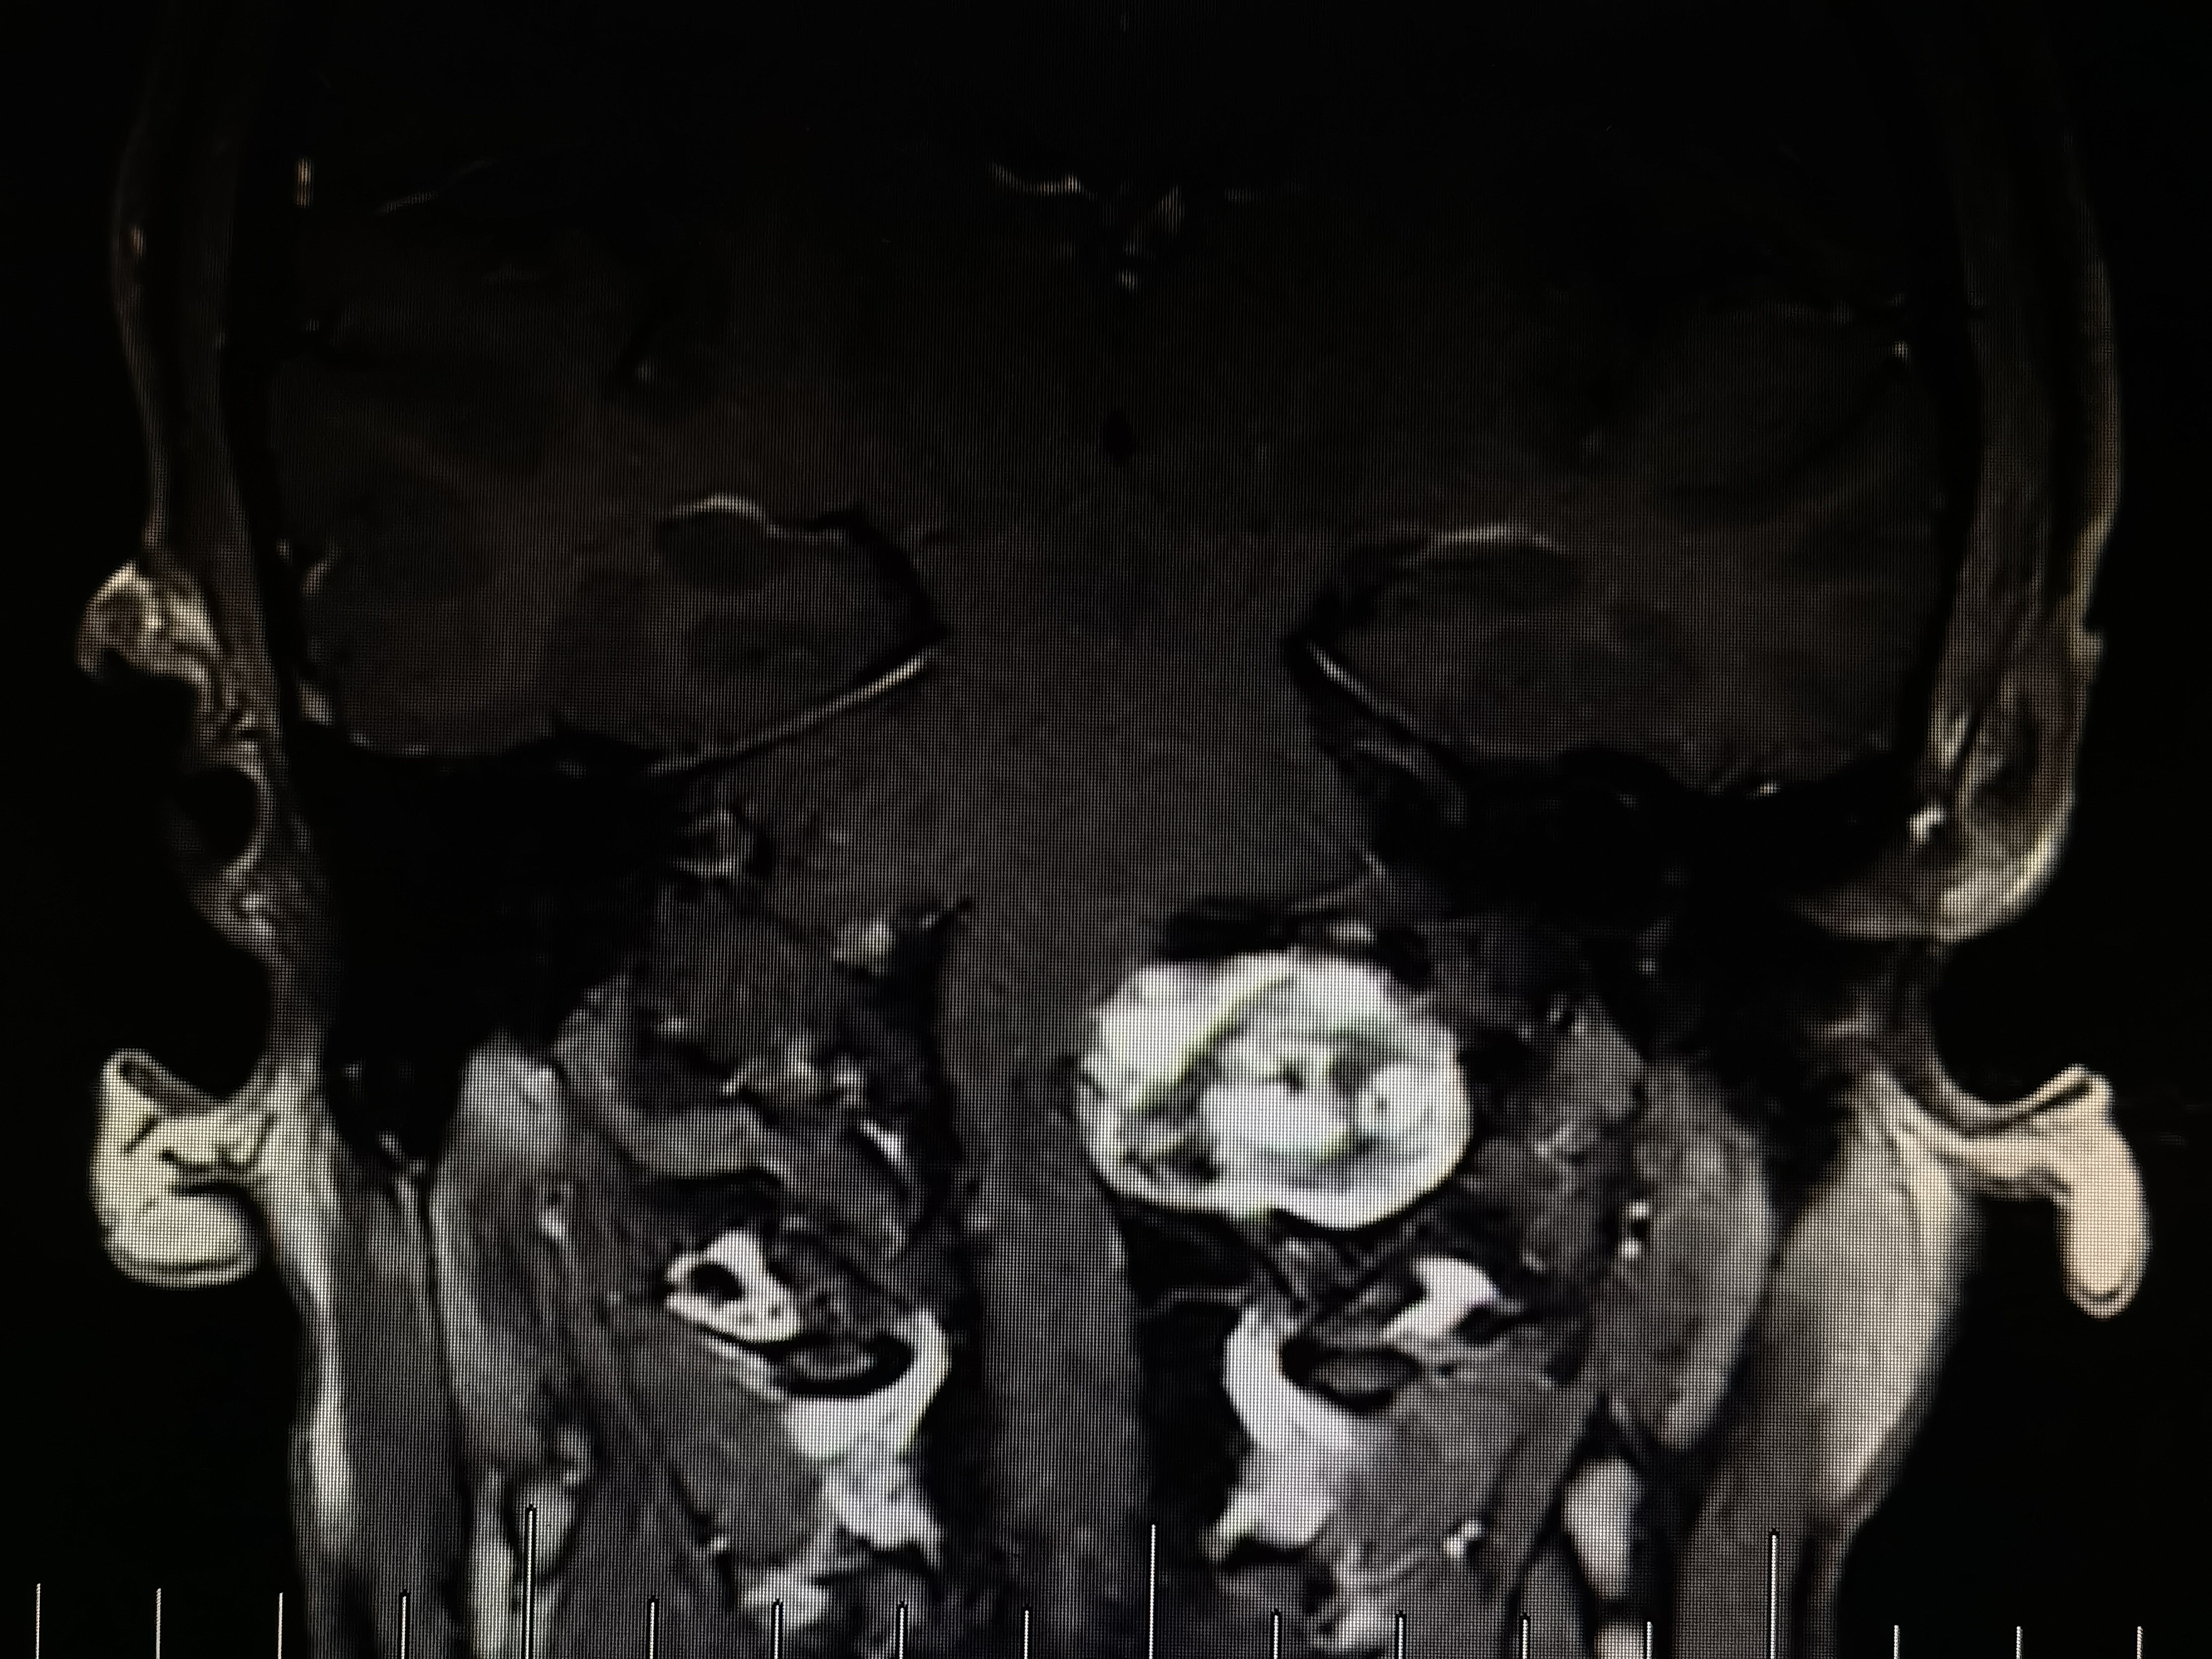

术前磁共振